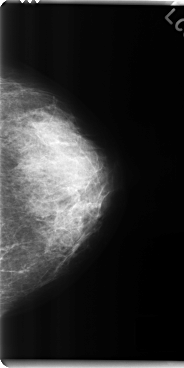

C_0284_1.LEFT_CC

LEFT_CC LINES 4784 PIXELS_PER_LINE 2392 BITS_PER_PIXEL 12 RESOLUTION 50 NON_OVERLAY